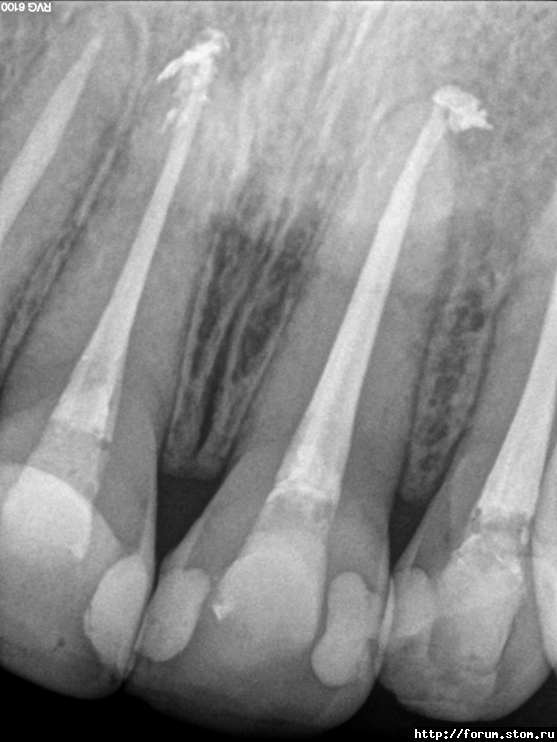

natikkk Опубликовано 6 ноября, 2011 Автор Поделиться Опубликовано 6 ноября, 2011 Делюсь радостью Тот же пациент через 10.5 месяцев после завершения лечения, жалобы отсутствуют Ссылка на комментарий

Снежана Опубликовано 6 ноября, 2011 Поделиться Опубликовано 6 ноября, 2011 прекрасный результат. поздравляю доктор! Ссылка на комментарий

Джима Опубликовано 7 ноября, 2011 Поделиться Опубликовано 7 ноября, 2011 Здорово как! Как будто не этот зуб к хирургу почти отправили. Ссылка на комментарий

natikkk Опубликовано 7 ноября, 2011 Автор Поделиться Опубликовано 7 ноября, 2011 Отличная работа! Сколько пац ходил с каласептом и чем потом пломбировали?Еще раз спасибо! На Каласепте в общей сложности ходил месяца 1.5, меняла его за это время вроде раза 3, мыла, звучила. Окончательная пломбировка- Термафил Ссылка на комментарий